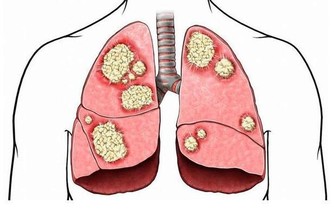

3. 你最近遭受過流感

感染流感後,至少一年內,心臟病發作的風險會增加6倍。

所以,如果你感冒或流感後感到呼吸困難,請立即去醫院。

因為某些細菌和病毒感染可能會進入你的心臟,導致心臟病甚至心力衰竭。